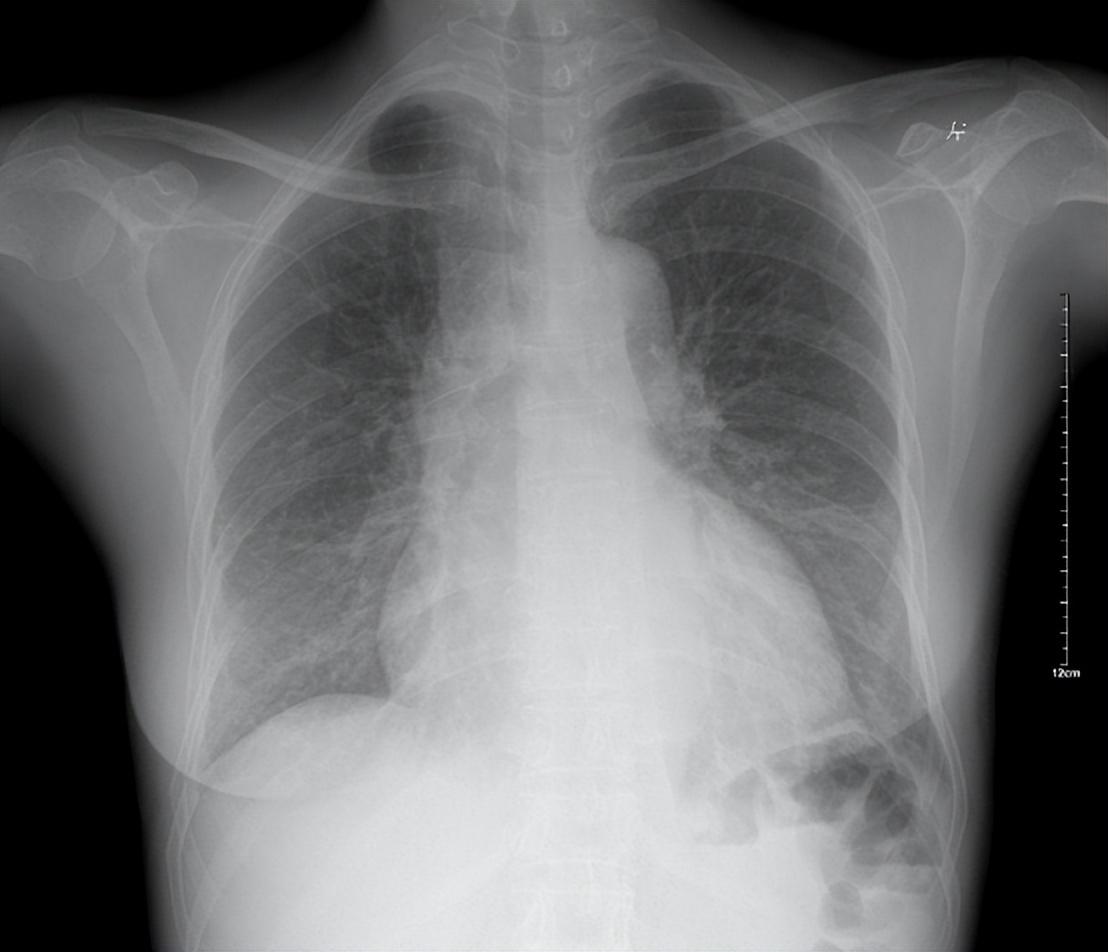

5)少數但必須警惕:心衰/肺水腫/肺癌等

別自己嚇自己,但也別硬扛。

如果出現以下情況,請別拖:

- 粉紅色泡沫痰 + 呼吸困難(警惕心衰/肺水腫)

- 痰中帶血 或反覆血絲痰(需排查腫瘤、結核、支擴等)

- 持續咳嗽 >3 周,且逐漸加重

- 明顯消瘦、低熱、盜汗

- 胸痛、氣短越來越重

這時候“化痰偏方”沒意義,應該先明確病因:胸片/CT、肺功能、心臟評估等。